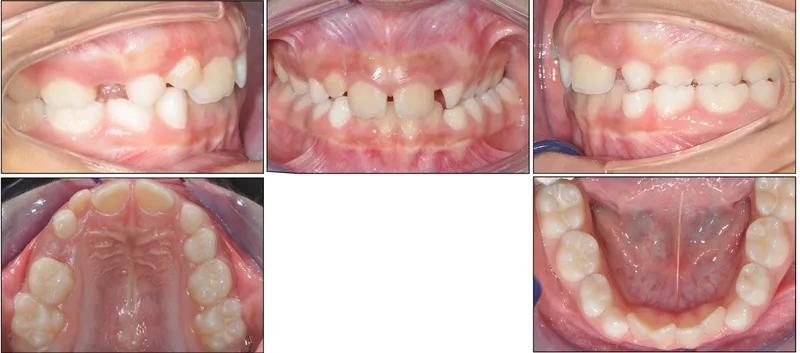

Espansore palatale

Il disgiuntore è un'apparecchiatura fissa che viene attivata gradualmente per ampliare la mascella superiore, sfruttando la plasticità ossea tipica dell'età evolutiva.

L'espansione palatale è più efficace prima della fusione della sutura palatina mediana, che avviene nella tarda adolescenza. Prima si interviene, migliori i risultati.